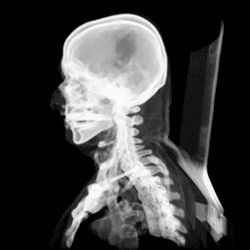

The skull, or cranium, is typically a bony enclosure around the brain of a vertebrate.[1][2] In some fish, and amphibians, the skull is of cartilage. The skull is at the head end of the vertebrate.

The human skull is the bone structure that forms the head in the human skeleton. It supports the structures of the face and forms a cavity for the brain. Like the skulls of other vertebrates, it protects the brain from injury.[6]

Development

At birth, the human skull is made up of 44 separate bony elements. During development, many of these bony elements gradually fuse together into solid bone (for example, the frontal bone). The bones of the roof of the skull are initially separated by regions of dense connective tissue called fontanelles. There are six fontanelles: one anterior (or frontal), one posterior (or occipital), two sphenoid (or anterolateral), and two mastoid (or posterolateral). At birth, these regions are fibrous and moveable, necessary for birth and later growth. This growth can put a large amount of tension on the "obstetrical hinge", which is where the squamous and lateral parts of the occipital bone meet. A possible complication of this tension is rupture of the great cerebral vein. As growth and ossification progress, the connective tissue of the fontanelles is invaded and replaced by bone creating sutures. The five sutures are the two squamous sutures, one coronal, one lambdoid, and one sagittal suture. The posterior fontanelle usually closes by eight weeks, but the anterior fontanel can remain open up to eighteen months. The anterior fontanelle is located at the junction of the frontal and parietal bones; it is a "soft spot" on a baby's forehead. Careful observation will show that you can count a baby's heart rate by observing the pulse pulsing softly through the anterior fontanelle.

The skull in the neonate is large in proportion to other parts of the body. The facial skeleton is one seventh of the size of the calvaria. (In the adult it is half the size). The base of the skull is short and narrow, though the inner ear is almost adult size.[15]